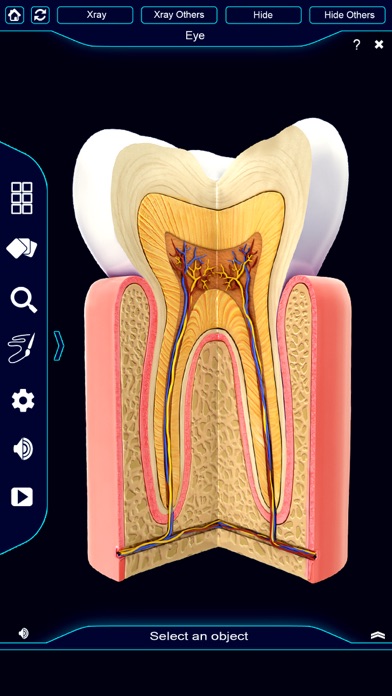

My Dental Anatomy app gives users an in depth look at the human Teeth allowing them to select , x-ray view, hide and show individual tooth Parts as well as , draw or white on screen and share screenshots, Audio pronunciation for all anatomical terms and more.

User can select each part separately to view name of the part or read related information.

- Xray mode

-Info panel

-Highly realistic Dental Anatomy 3D models.